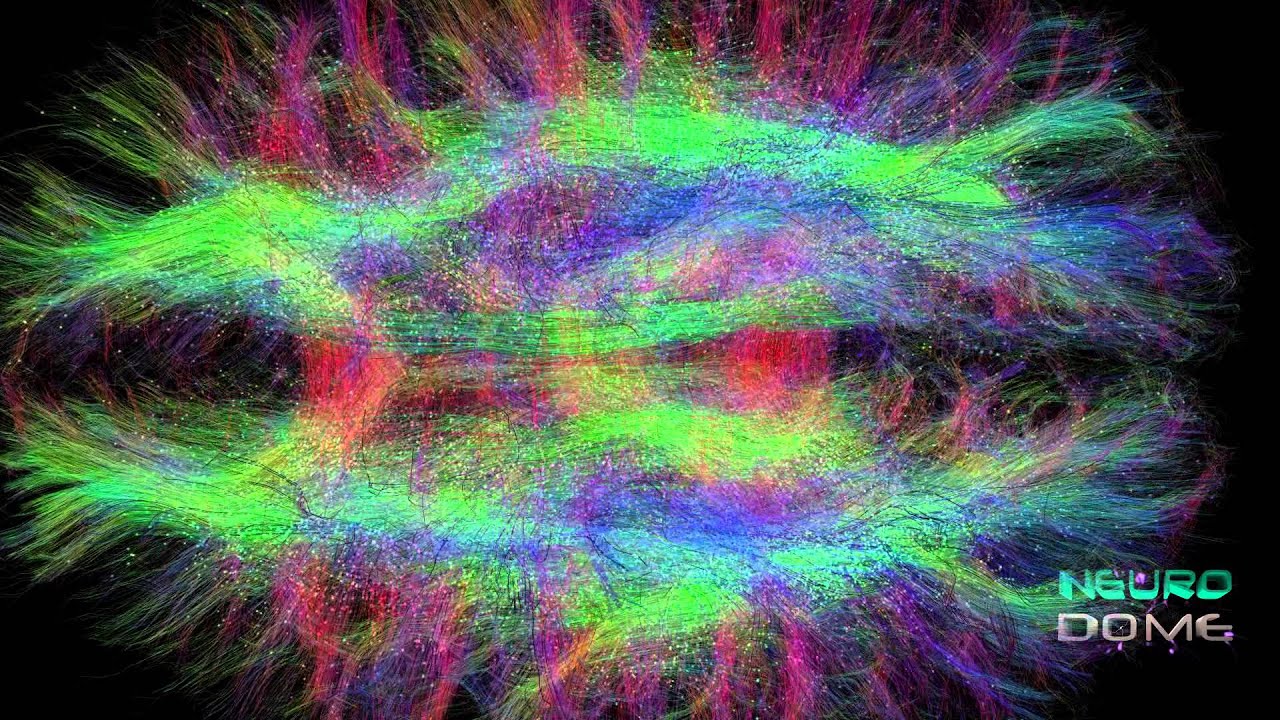

Diffusion Tensor Imaging (DTI) revealing connectivity in the brain

Diffusion MRI, also referred to as diffusion tensor imaging or DTI

Diffusion MRI, also referred to as diffusion tensor imaging or DTI

DTI Animation by @neuroscience_hub on instagram